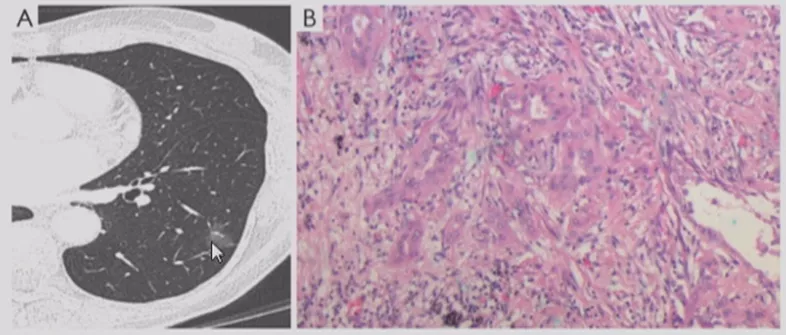

小细胞肺癌

小细胞肺癌以中央型多见,但是也有少数为周围型病灶。多为单个实性结节或肿块,可见分叶、毛刺、血管集束征、胸膜牵拉征。实际上我们很难从影像学上判断出小细胞肺癌的病理类型,往往是活检或者手术以后才能证实。如下图示,这属于I期的小细胞肺癌,进行手术的效果非常好。所以对于周围型小细胞肺癌,如果在结节很小的时候判断出来就做了手术,疗效非常好。我们知道小细胞肺癌是肺癌中治疗效果最差的,恶性程度是最高的。如果早期手术,仍然能够起到很好的效果。